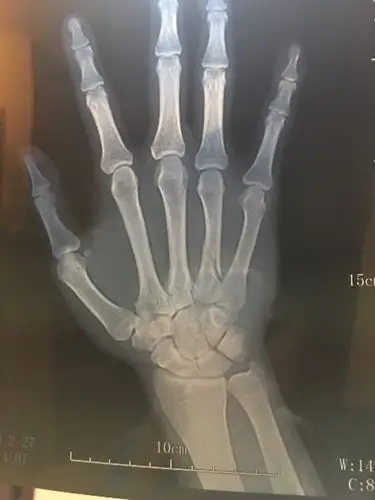

多发掌骨骨折例 [病例帖]

手掌骨第四根骨折,多久可以干重体力活呀?不干活怎么办?